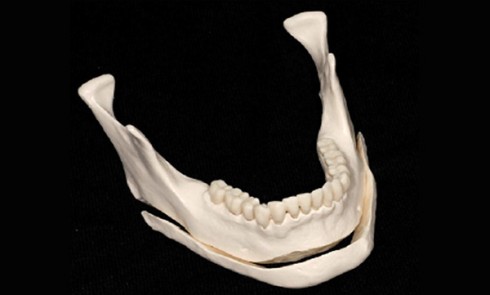

Article réservé à nos abonnés Ostéotomies du rebord mandibulaire

L’anatomie du rebord mandibulaire présente deux structures majeures qui sont le menton et l’angle mandibulaire. Les ostéotomies conventionnelles ont longtemps...